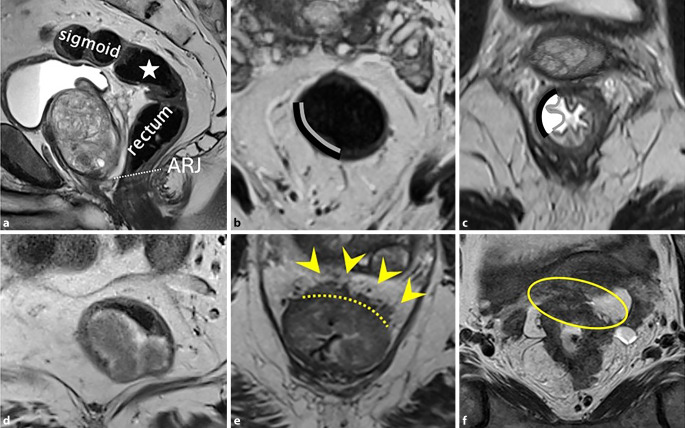

Background: Imaging, specifically magnetic resonance imaging (MRI), has long been the cornerstone for staging rectal cancer. In contrast, computed tomography (CT) is the standard for colon cancer staging. Primary staging is essential for individualized risk stratification and therapy planning.

Results: TNM staging includes local tumor extension as well as the presence of lymph node and distant metastases. For local tumor extension, MRI is very well suited for rectal cancer. In colon cancer, CT shows significant limitations regarding the sensitivity of differentiating individual stages. Lymph node metastases can pose a major challenge for both MRI and CT, which has led to the definition of several malignancy criteria. The detection of distant metastases remains primarily within the domain of CT, except for liver metastases.

Conclusions: Depending on tumor location, either MRI or CT is recommended for primary staging of colorectal cancer, and a combination of both modalities may also be appropriate. Accurate assessment of the primary tumor, lymph nodes, and organs using imaging is an essential component of the therapeutic approach to colorectal cancer.